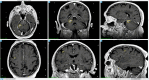

Case description: This report details the case of a 75-year-old male diagnosed with MCC following surgical excision of an inguinal mass, with subsequent adjuvant radiotherapy. Four months post-surgery, imaging revealed a pancreatic nodule and two cerebral lesions. The patient underwent Gamma Knife® stereotactic radiosurgery (GK-SRS) followed by adjuvant immunotherapy with avelumab. MRI follow-ups showed a significant reduction of the cerebellar lesion and full remission of the frontal lesion, with stable remission noted at one year. The patient remained asymptomatic and continued immunotherapy without neurological deficits.